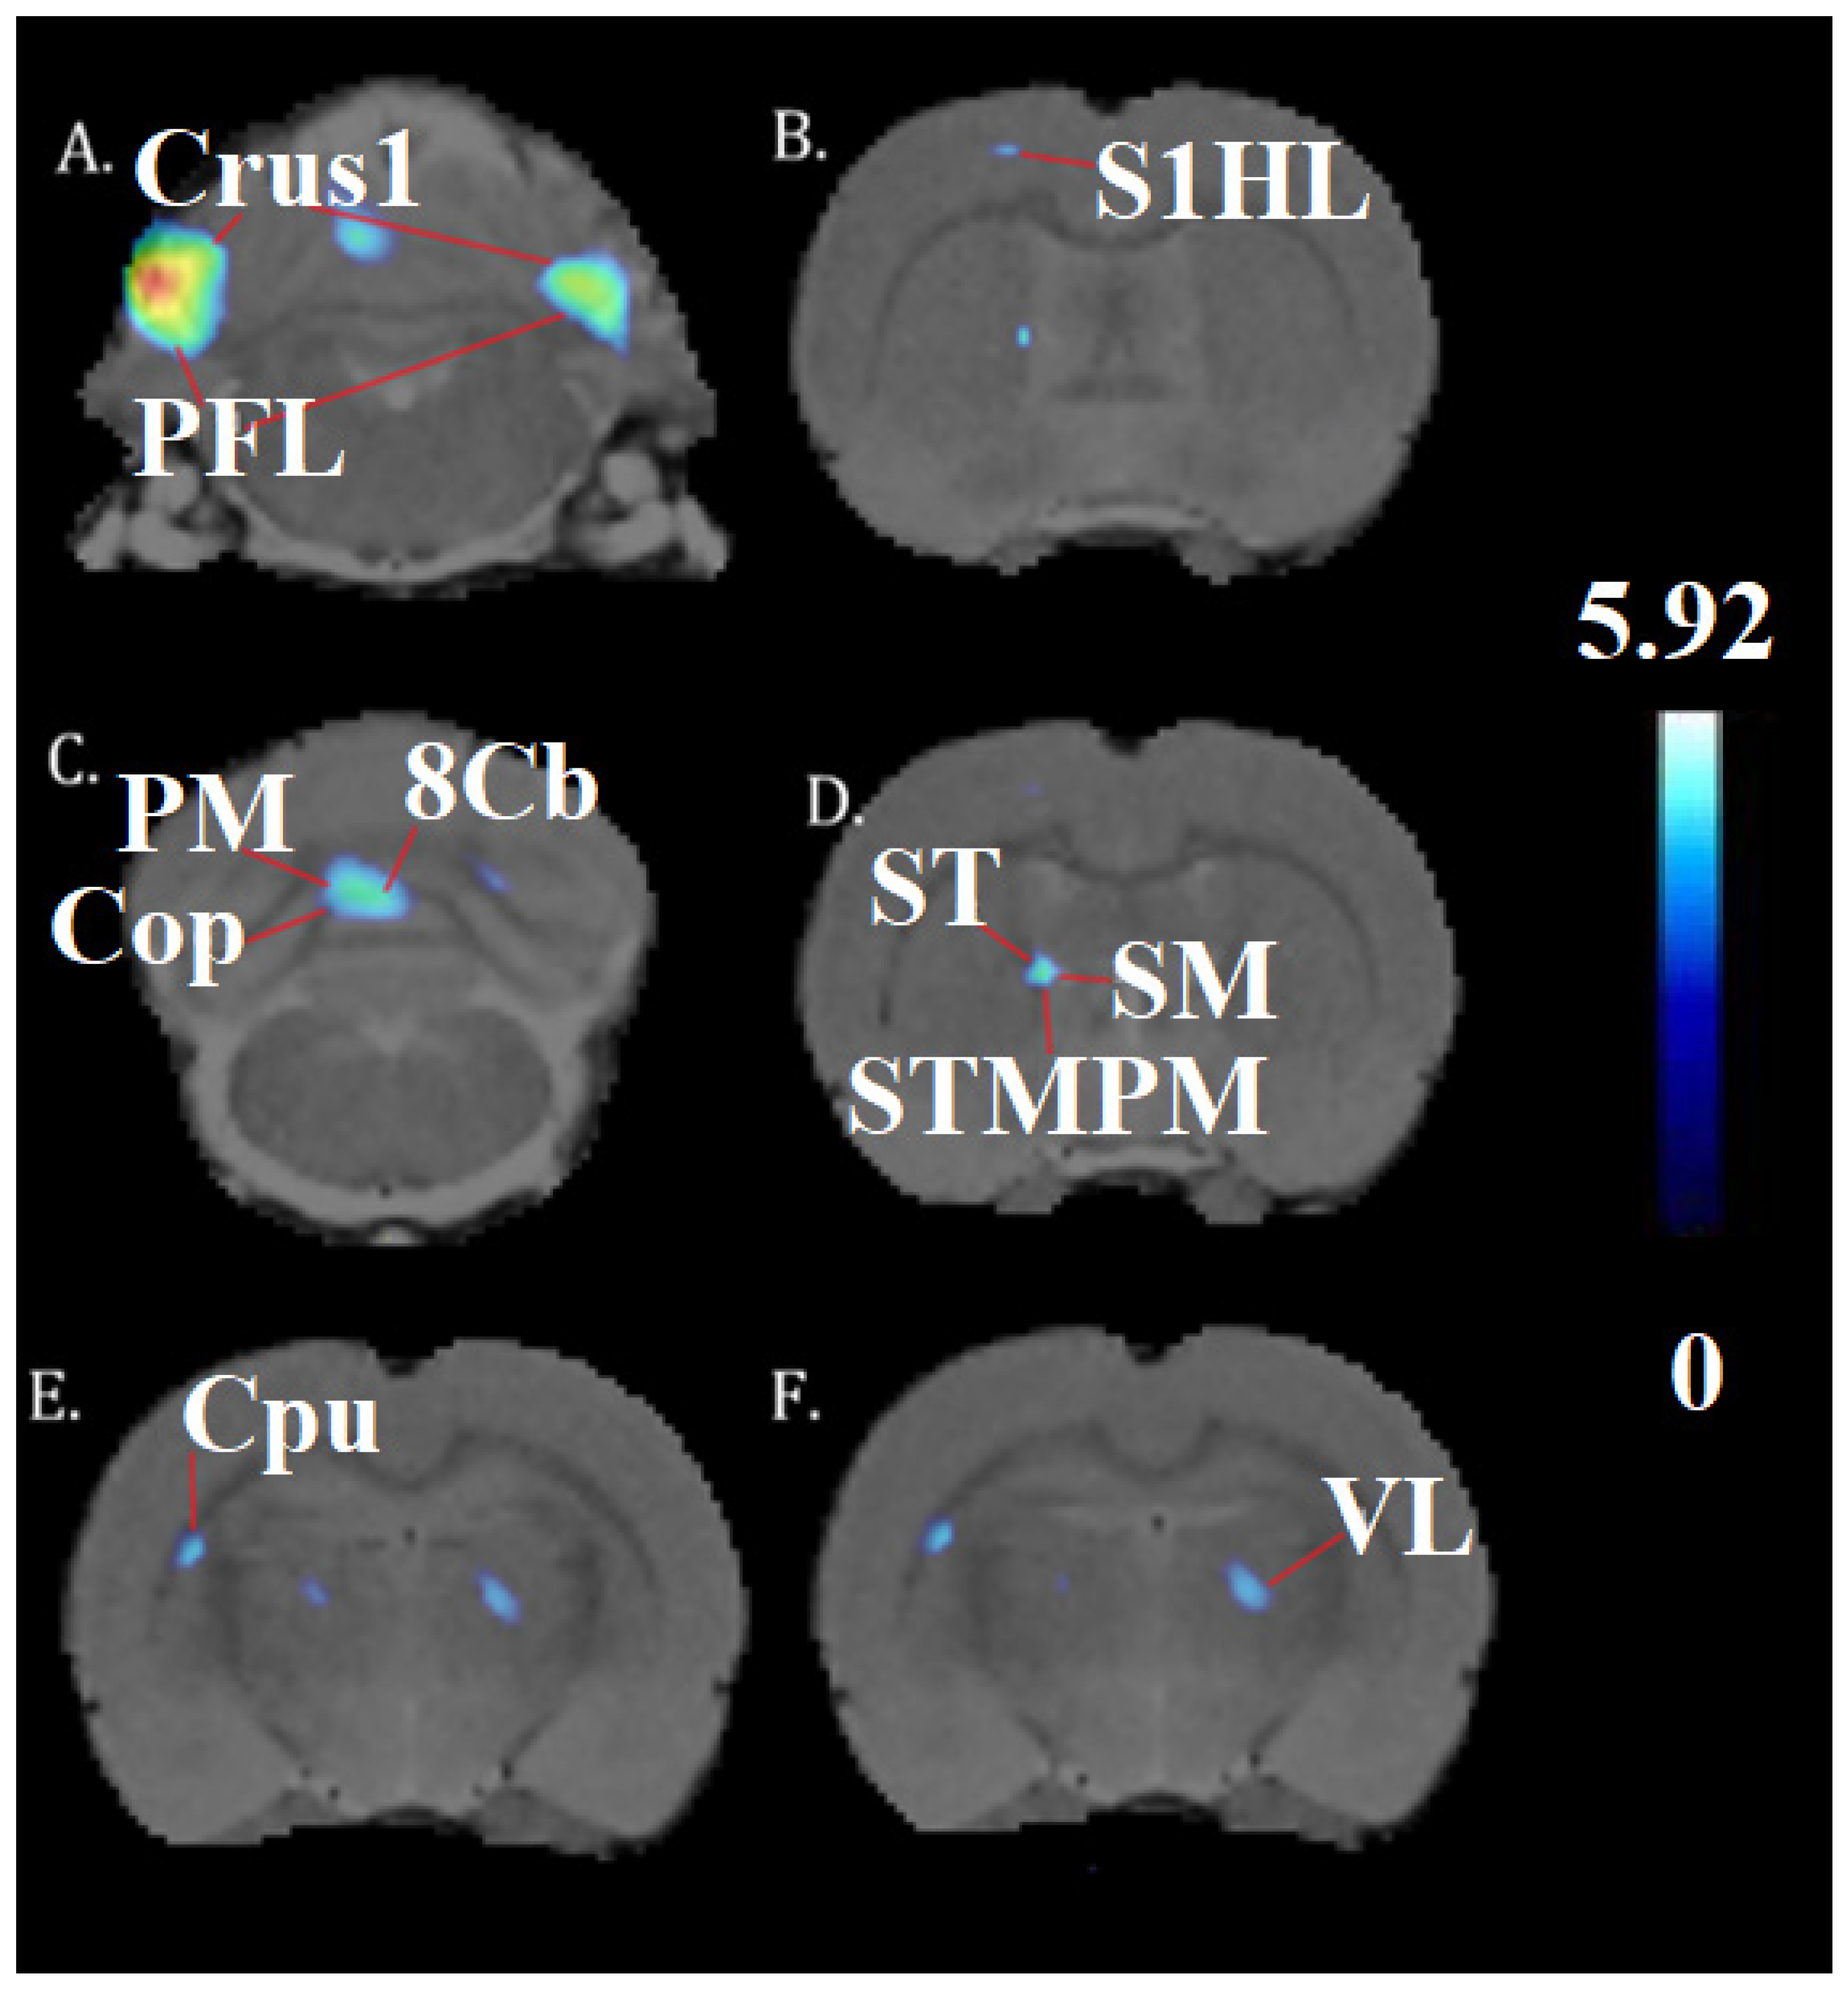

| Crus1, PFL | Cerebellum | −5.0 | 6.0 | −11.4 | 5.92 | 4.45 | 2496 |

| PFI, Crus1 | Cerebellum | 4.0 | 5.2 | −11.0 | 6.18 | 4.57 | 2175 |

| 8cb, PM, Cop | Cerebellum | −0.8 | 4.4 | −12.4 | 5.00 | 3.98 | 2103 |

| St, sm, stmpm | Stria terminalis, thalamus | −1.8 | 5.8 | −0.8 | 4.92 | 3.94 | 238 |

| CPu | midbrain | −4.4 | 4.6 | −2.4 | 4.68 | 3.80 | 193 |

| VL | Thalamus | 1.8 | 5.6 | −2.4 | 4.44 | 3.66 | 174 |

| S1HL | Somatosensory cortex | −2.2 | 1.8 | −0.4 | 4.06 | 3.42 | 58 |